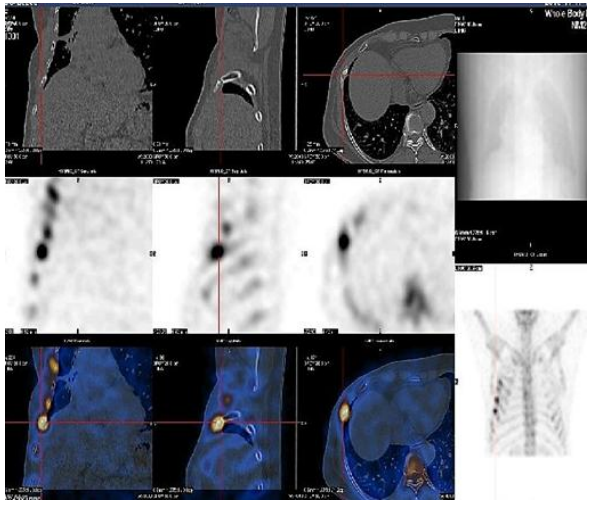

SPECT/CT integrates high-end ECT and spiral CT into a large-scale device. In addition to providing the organ tissue functional information reflected by ECT, it also offers the anatomical information of CT. Through the fusion imaging technology, functional images are overlaid with anatomical images, further enhancing the accuracy of disease diagnosis.

It is the preferred method for early diagnosis of malignant tumor bone metastasis. It can be used for disease staging, evaluation of bone pain, prognosis assessment, efficacy observation, and detection of high-risk sites for pathological fractures. SPECT/CT fusion imaging greatly improves diagnostic sensitivity, specificity, and localization accuracy.